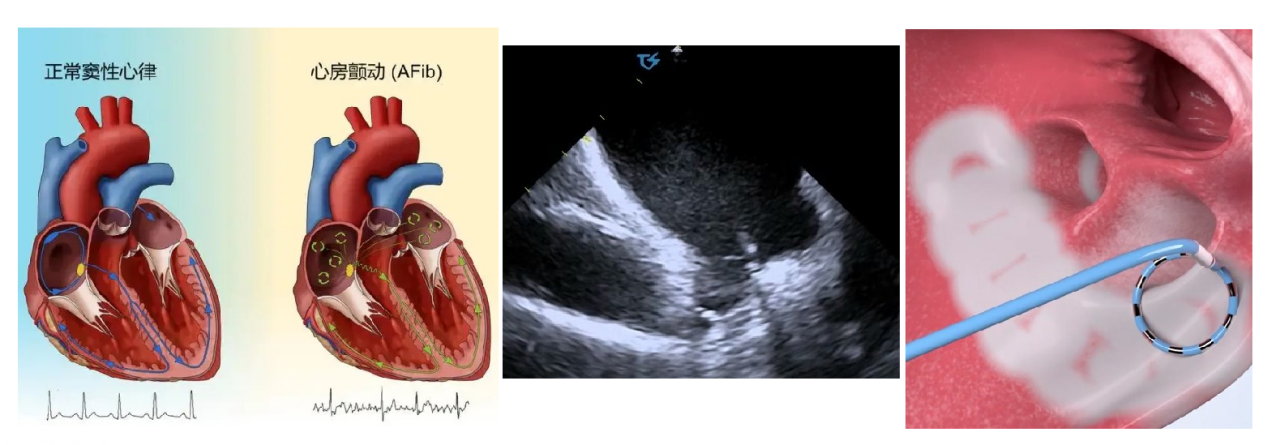

心房颤动(简称房颤)是临床中最常见的一种心律失常,发病率随着年龄的增加而逐渐增高,显著增加患者死亡、卒中、心力衰竭(心衰)、认知功能障碍和痴呆风险,严重影响患者生活质量。心腔内超声导管引导下的脉冲消融是一种微创手术,通过在心腔内使用超声导管,医生能够实时监测和构建心脏的三维结构,精确地定位到引起房颤的异常电生理活动区域。

这项技术的优势在于它能够在极低X射线的情况下,安全、准确地引导消融导管到达目标位置,同时房颤脉冲消融技术(PFA)脉冲电场消融术是房颤导管消融领域一种全新的安全、高效的治疗方法。其原理是通过高压脉冲电场,造成细胞不可逆的电穿孔,最终导致细胞程序性死亡。与传统的治疗方式相比,房颤脉冲电场消融安全性更高,具有一定的组织选择性,能显著减少心房食道瘘、肺静脉狭窄、心包填塞等并发症的发生风险。同时脉冲电场消融手术时间短、多点同时放电,每次放电仅需2-4秒,效率高,与其他消融方式相比,能将整体手术时间缩短一半,患者术中痛感减少,手术流程更简单,患者术后恢复更快,是房颤治疗的又一把利剑。

心腔内超声指导的房颤脉冲消融